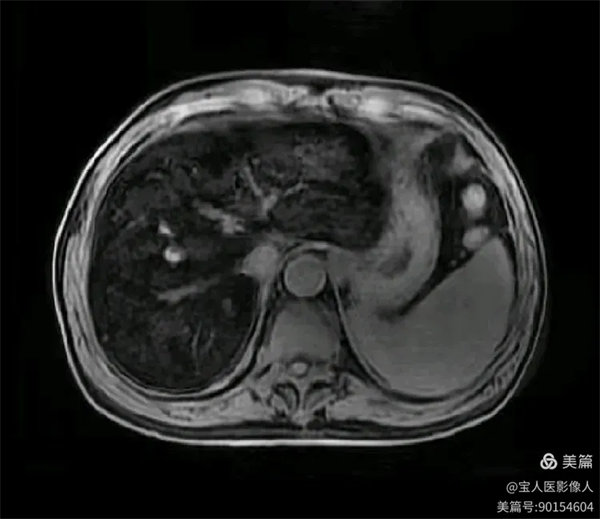

T2WI冠位,軸位,肝實質信號明顯降低,呈“”黑肝征”,而脾臟信號正常。